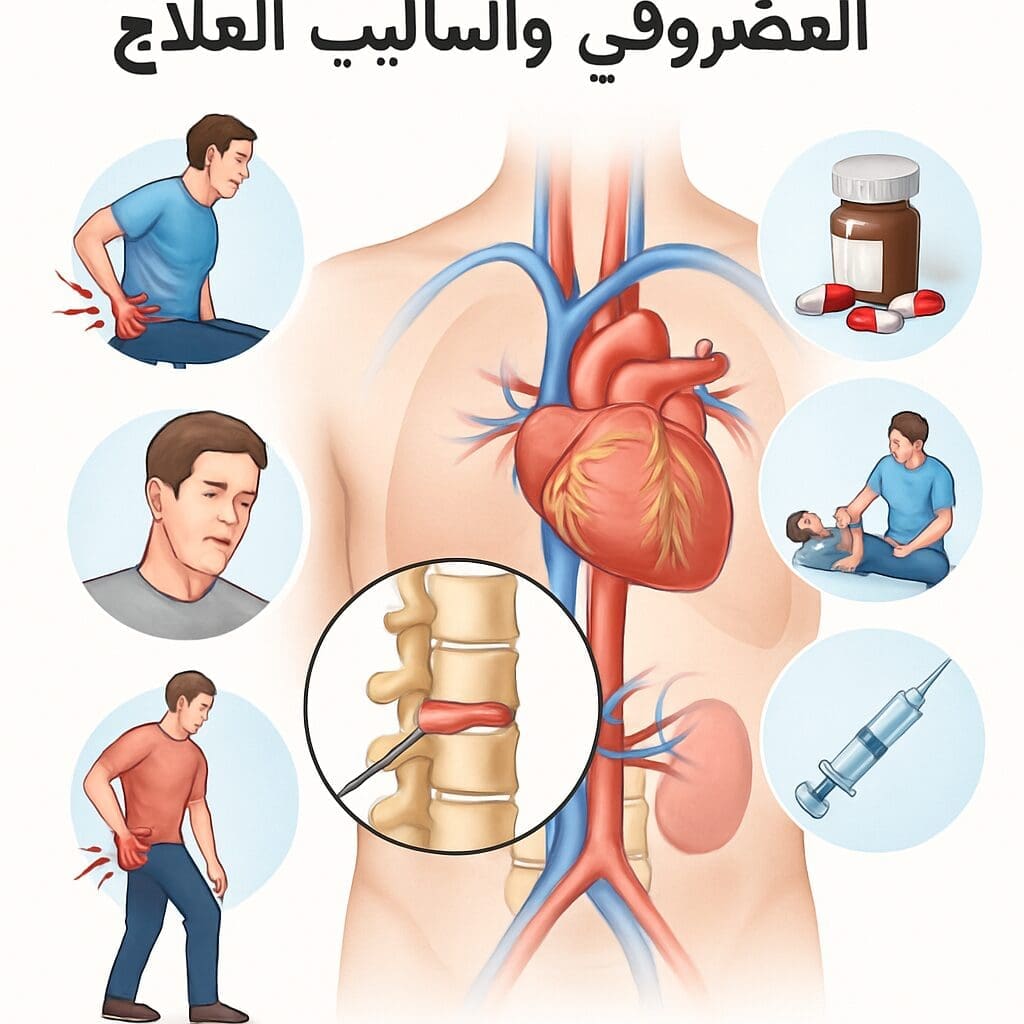

نغطي كل التخصصات الطبية

استیعاب کافة الحالات الطبیة لشمولیة التخصصات

مقالات طبية من مساهمات الأطباء